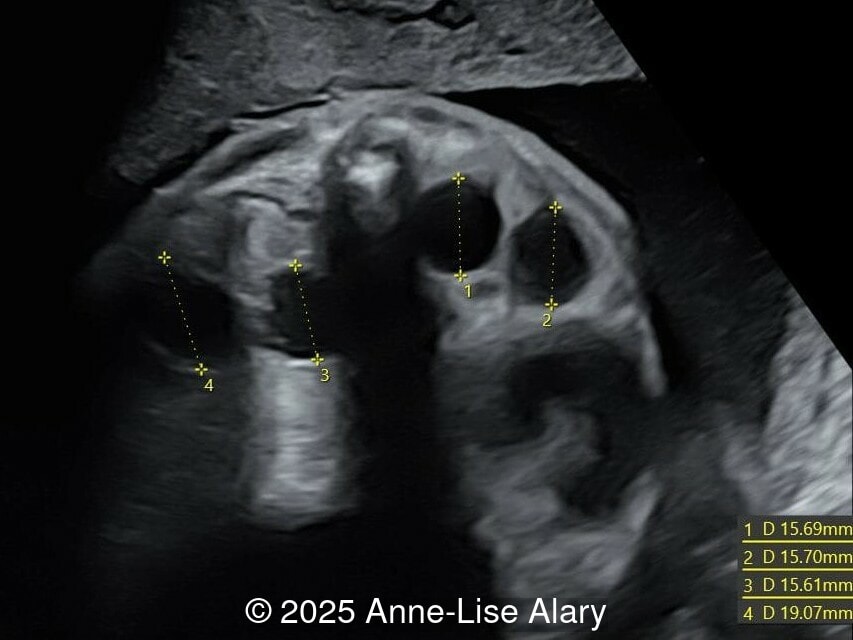

Image 2

Axial image of the abdomen

Image 3 Axial image of the abdomen

Our prenatal ultrasound revealed a male fetus with megabladder, dilation of both ureter and kidneys, and thinned kidney parenchyma consistent with Lower Urinary Tract Obstruction (LUTO).  Additional findings suspected on ultrasound and confirmed on computed tomography included:

The diagnosis of PBS is often made in the second trimester of pregnancy, although it has been described as early as 11 weeks of gestation [20]. The most frequent ultrasound findings are a large, thin-walled bladder accompanied by bilateral hydroureter/hydronephrosis, dysplastic kidneys with echogenic renal parenchyma and renal cortical cysts, and abdominal wall laxity which is better viewed after bladder decompression [21]. Cryptorchidism can be detected prenatally by 28 to 30 weeks gestation when the testes descend into scrotum. There may be a patent urachus, visible as a cystic connection between bladder and umbilicus. Oligohydramnios is a frequent finding, which makes it difficult to visualize the associated anomalies.